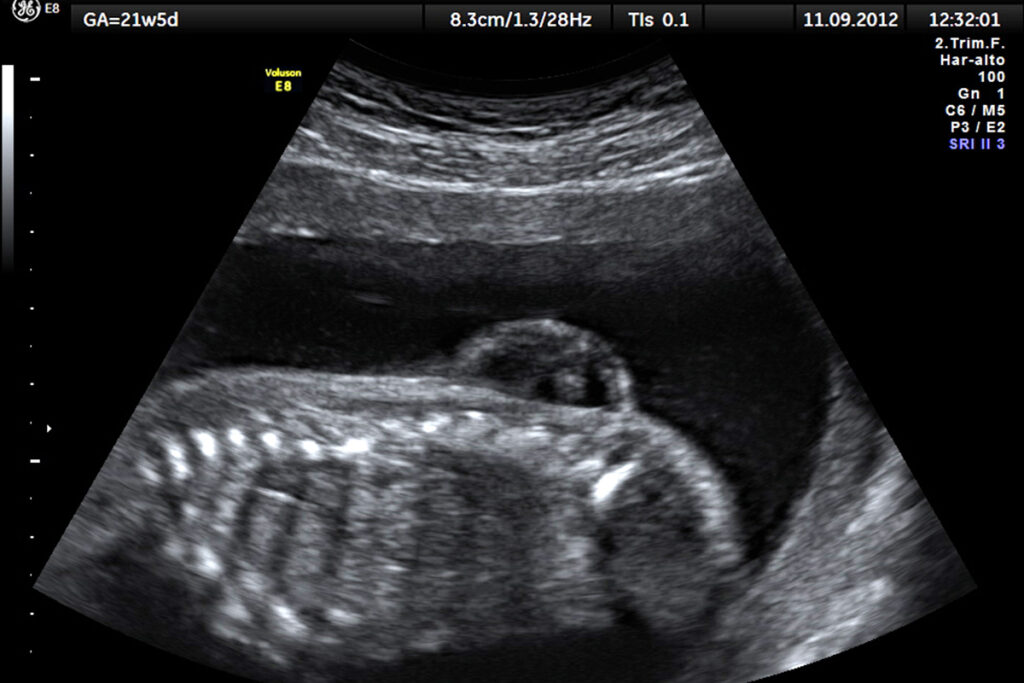

Spina bifida с латыни буквально переводится как «расщепление позвоночника». Это аномалия неизвестного происхождения, которая чаще всего появляется на ранних этапах беременности: при формировании у плода позвоночника некоторые позвонки не закрываются костной тканью, и в результате нервы и оболочки спинного мозга остаются открытыми — как раз из-за этого на спине может появиться грыжа.

Изображение: Wikimedia Commons